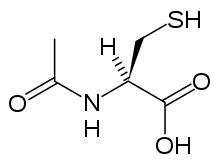

Acetylcysteine

Acetylcysteine, also called N-acetylcysteine or NAC, works to reduce paracetamol toxicity by replenishing body stores of the antioxidant glutathione. Glutathione reacts with the toxic NAPQI metabolite so that it does not damage cells and can be safely excreted.[67] NAC was usually given following a treatment nomogram (one for patients with risk factors, and one for those without) but the use of the nomogram is no longer recommended as the evidence base to support the use of risk factors was poor and inconsistent and many of the risk factors are imprecise and difficult to determine with sufficient certainty in clinical practice.[68] Cysteamine and methionine have also been used to prevent hepatotoxicity,[69] although studies show that both are associated with more adverse effects than acetylcysteine.[20] Additionally, acetylcysteine has been shown to be a more effective antidote, particularly in patients presenting greater than 8 hours post-ingestion[70] and for those who present with liver failure symptoms.[61]

If the person presents less than eight hours after paracetamol overdose, then acetylcysteine significantly reduces the risk of serious hepatotoxicity and guarantees survival.[20] If acetylcysteine is started more than 8 hours after ingestion, there is a sharp decline in its effectiveness because the cascade of toxic events in the liver has already begun, and the risk of acute liver necrosis and death increases dramatically. Although acetylcysteine is most effective if given early, it still has beneficial effects if given as late as 48 hours after ingestion.[71] If the person presents more than eight hours after the paracetamol overdose, then activated charcoal is not useful, and acetylcysteine is started immediately. In earlier presentations, charcoal can be given when the patient arrives and acetylcysteine is initiated while waiting for the paracetamol level results to return from the laboratory.[20]